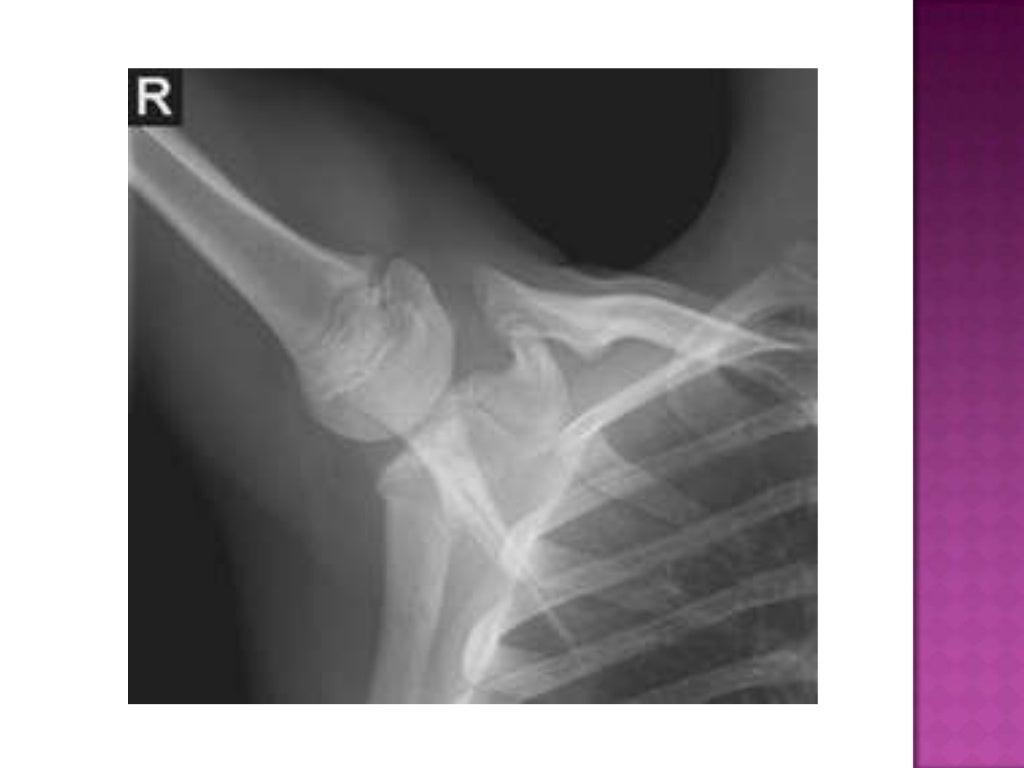

Anterior humeral line Radiology Case Radiology Which Joints Are Included On A Humerus Radiograph Articulates with the glenoid cavity of the scapula. Proximal (refer to shoulder joint article for more details): Distal (refer to elbow joint. See a charcot joint of the shoulder here. Lateral radiograph of the humerus with labels. Arises from the third part of the. However, it can also be taken in the supine position in the. The lateral view of. Which Joints Are Included On A Humerus Radiograph.